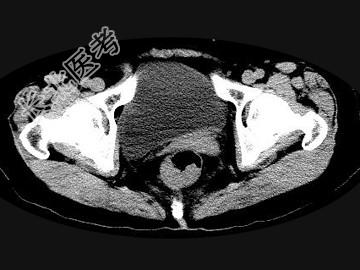

- 单项选择题男,56岁, 排便形状改变,便后不尽感, CT检查如图所示,下列说法正确的是 ( )

A、肠壁上有蒂状新生物

B、其表面光滑,边界清楚

C、肠腔未见狭窄

D、此为直肠息肉

E、此为直肠癌